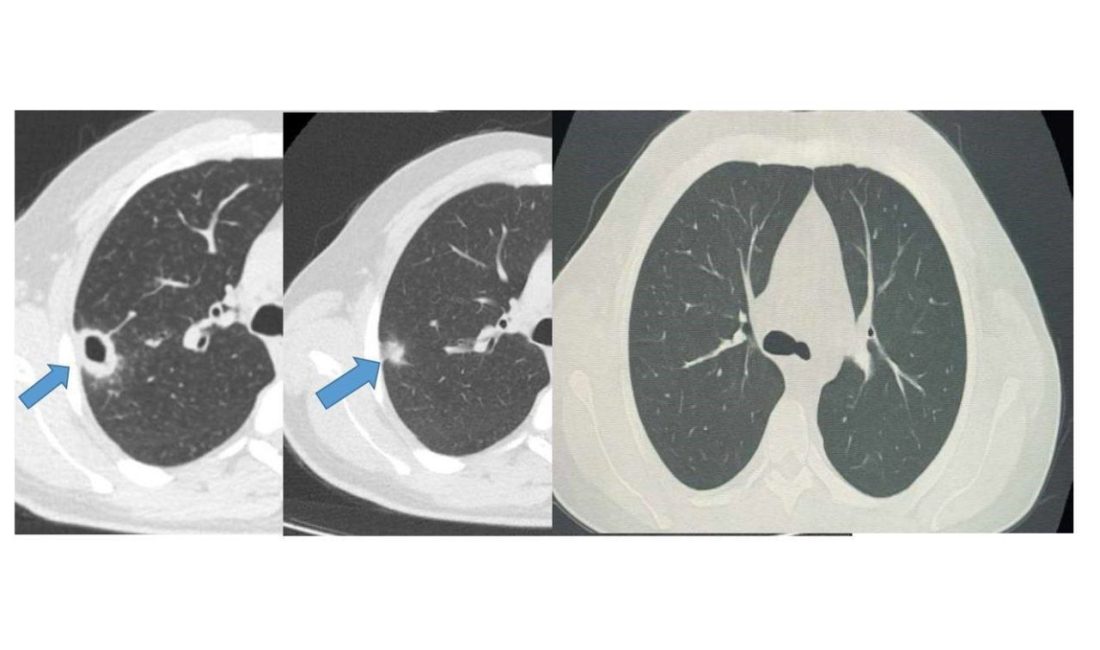

Bayburt Devlet Hastanesine öksürük ve balgam şikayetiyle başvuran 50 yaşındaki hastanın akciğerinde kitle benzeri bir doku tespit edildi. Yapılan tetkikler sonucu ciddi bir hastalık olmadığı belirlenen hasta, erken tanı ve doğru tedavi sayesinde sağlığına kavuştu.

Göğüs Hastalıkları Uzmanı Uzm. Dr. Hilal Sayma tarafından muayene edilen hastaya ileri tetkik amacıyla bronkoskopi işlemi uygulandı. Bronkoskopi sonucunda lezyonun kanser veya tüberküloz gibi ciddi hastalıklarla ilişkili olmadığı belirlenerek, hasta için uygun tedaviye başlandı.

İki haftalık tedavi sürecinin sonunda yapılan kontrollerde lezyonun neredeyse tamamen gerilediği görüldü. Sağlığına kavuşan hastanın taburcu edildiği ve durumunun iyi olduğu öğrenildi.